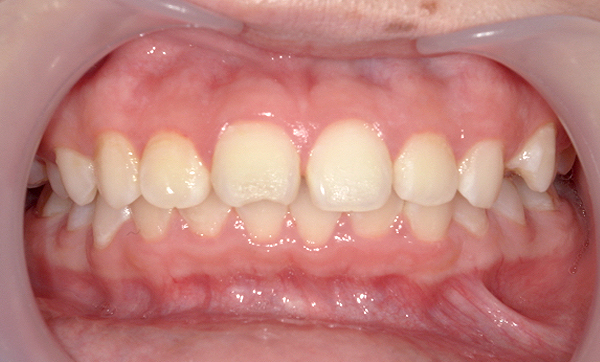

| 治療前 | 治療後 |

|---|---|

|